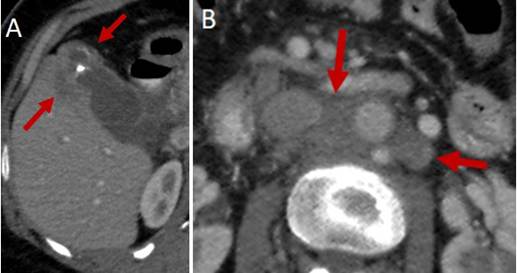

La ecografía abdominal debe hacer sospechar un CVB cuando hay engrosamiento focal e irregular de la pared de la vesícula o cuando el espesor es mayor de 10 mm. La TC y la RNM son más útiles para evaluar la extensión de la enfermedad o cuando hay masas vesiculares de buen tamaño 49 (Figuras 2 y 3). Cuando el diagnóstico se sospecha de forma intraoperatoria, el cirujano se enfrenta a una situación compleja en la que tenía programada solo una colecistectomía, y que debe ser analizada caso a caso, debido a las implicaciones de una cirugía mayor en un paciente no informado de la misma y con riesgo de morbilidad y mortalidad. Si la patología confirma el diagnóstico, se realizará la estadificación y toma de decisiones según la misma 50.

Cuando el compromiso neoplásico afecta la lámina propia, respetando la capa muscular, corresponde a un estadio T1a y no requiere intervenciones adicionales a la simple colecistectomía. Ante la presencia de estadios T1b o más, se deben realizar estudios imagenológicos de estadificación clínica, que deben incluir imágenes de alta resolución de tórax, abdomen y pelvis, en busca de linfadenopatías regionales o metástasis a distancia (Figuras 2, 3 y 4), además se debe considerar la realización de una laparoscopia (Figura 5) 30. La estadificación del CVB se muestra en la Tabla 253.